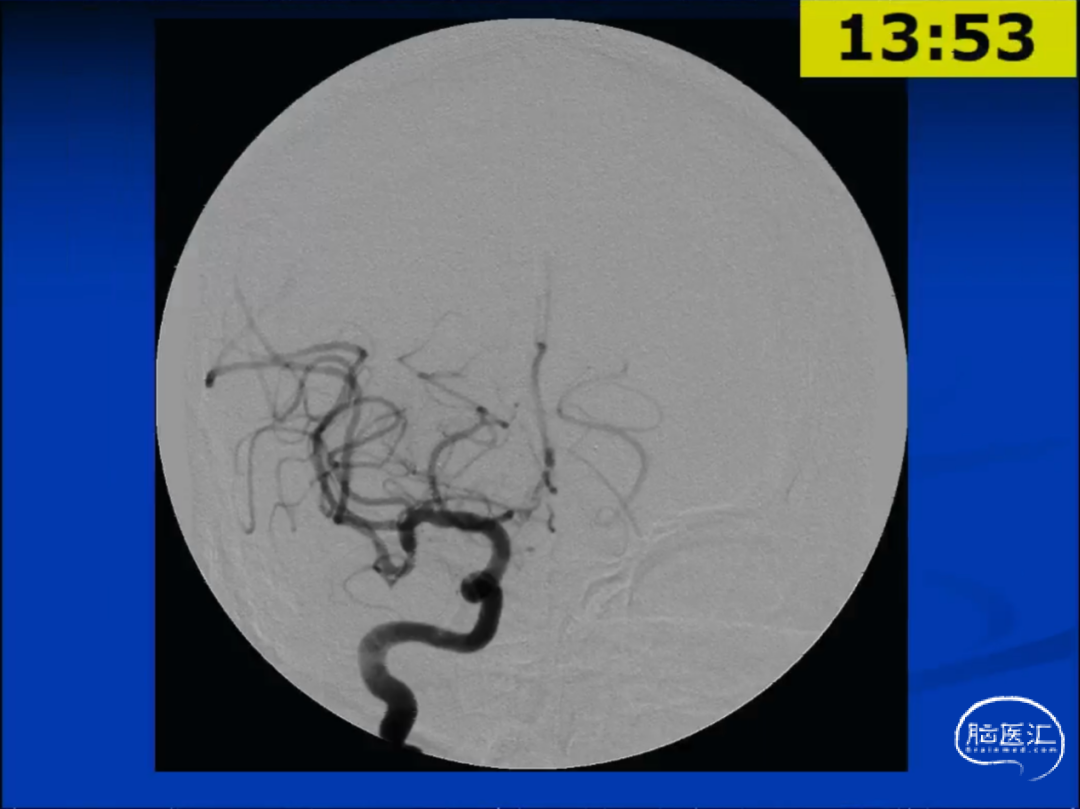

举例说明,70岁女性,11mm的前交通动脉动脉瘤(未破裂型),宽颈,形态不规则。

对于该动脉瘤,使用FD有较大的覆盖侧枝血管(Jailing)的风险。最终选择了球囊辅助的弹簧圈栓塞术,达到了完整的栓塞。

弹簧圈的优势在于其可塑性性,而球囊/支架辅助弹簧圈技术可以减少弹簧圈的逃逸。